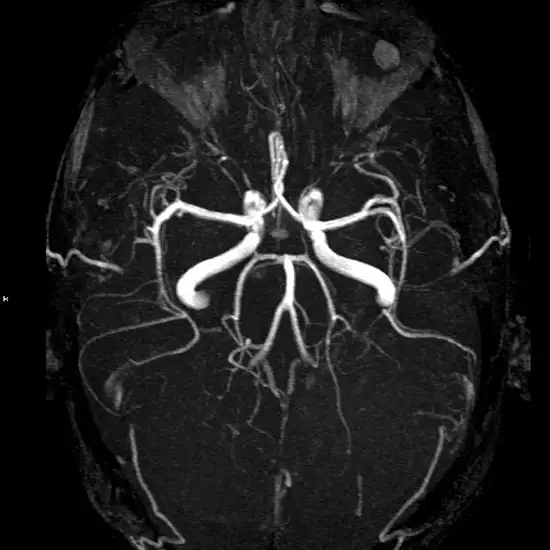

MR Angiography Brain T2W imagining is one of the basic pulse sequences on MRI. During the test, images are produced by using longer TE (Time to Echo) and TR (Repetition Time) times and are predominately determined by the T2 properties of tissue.

Through the T2-weighted MRI scans, doctors seek information about disease burden or lesion load or the total amount of lesion area. It is performed to detect paramagnetic deoxyhemoglobin, methemoglobin, or hemosiderin in lesions and tissues.

A patient is asked to lie on his back on a flat surface which is slipped into the magnetic resonance imaging scanner. A special dye is injected into the bloodstream to have a clear vision of the blood vessels.

MR Angiography Brain T2W is a Magnetic Resonance Imaging non-invasive medical diagnostic tool for the detection of abnormalities in the brain by pulse sequence. MR Angiography Brain T2W is used to show brain abnormalities in more detail.